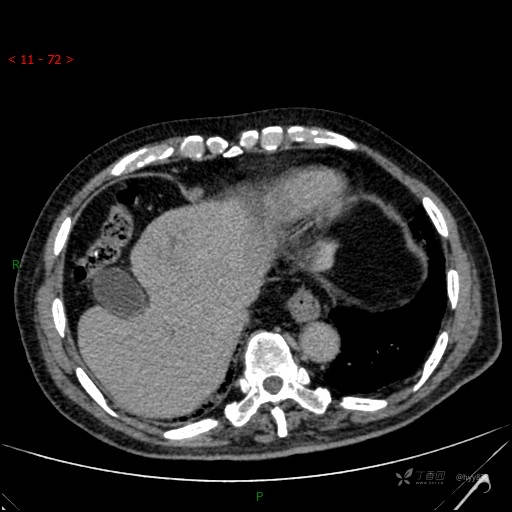

年龄:71岁

性别:男

简要病史: 间断发热、咳嗽3天,超声发现肝占位

临床诊断:肝占位

肝脏CT平扫